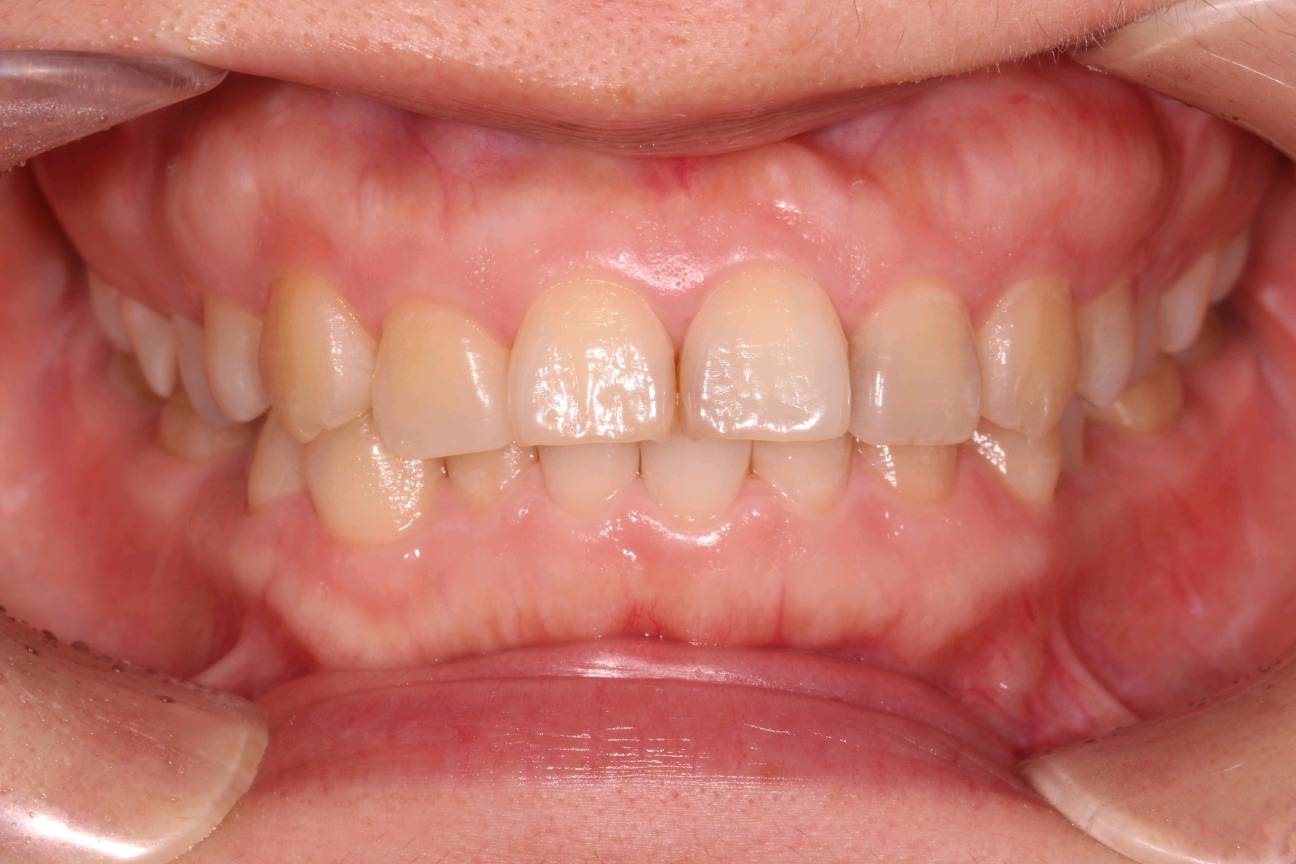

客户诉牙齿进食冷热酸痛敏感,检查发现各牙邻接面龋坏,告知患者各种备选修复材料的优缺点、相应修复费用和修复时间、可能的复诊次数和并发症,患者选择了嵌体修复。

0.1%的聚维酮碘溶液局部消毒,涂表麻膏,4%盐酸阿替卡因肾上腺素注射液0.8ml局部浸润麻醉,等待麻药生效后。去净腐质,基牙预备基牙预备,排龈,精修,CEREC扫描,比色,CEREC制作嵌体,试戴后边缘密合,符合各种对修复体的质量和设计要求,患者满意,同意粘固。消毒基牙和修复体,酸蚀冲洗,隔湿,吹干,粘接做永久固定,调合抛光,交代注意事项,常规医嘱,按时复诊,客户表示一次就诊方便快捷,很满意。